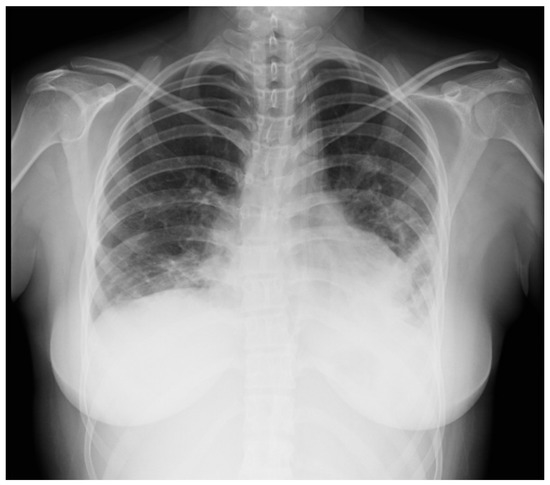

2.3. Case 3